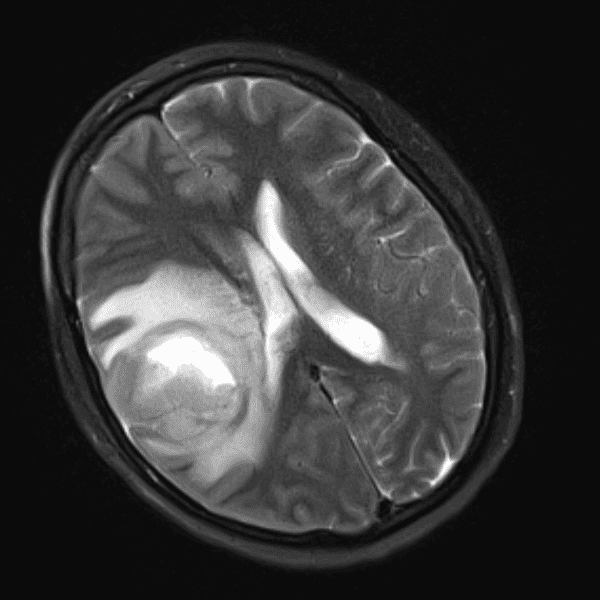

Classic Cases